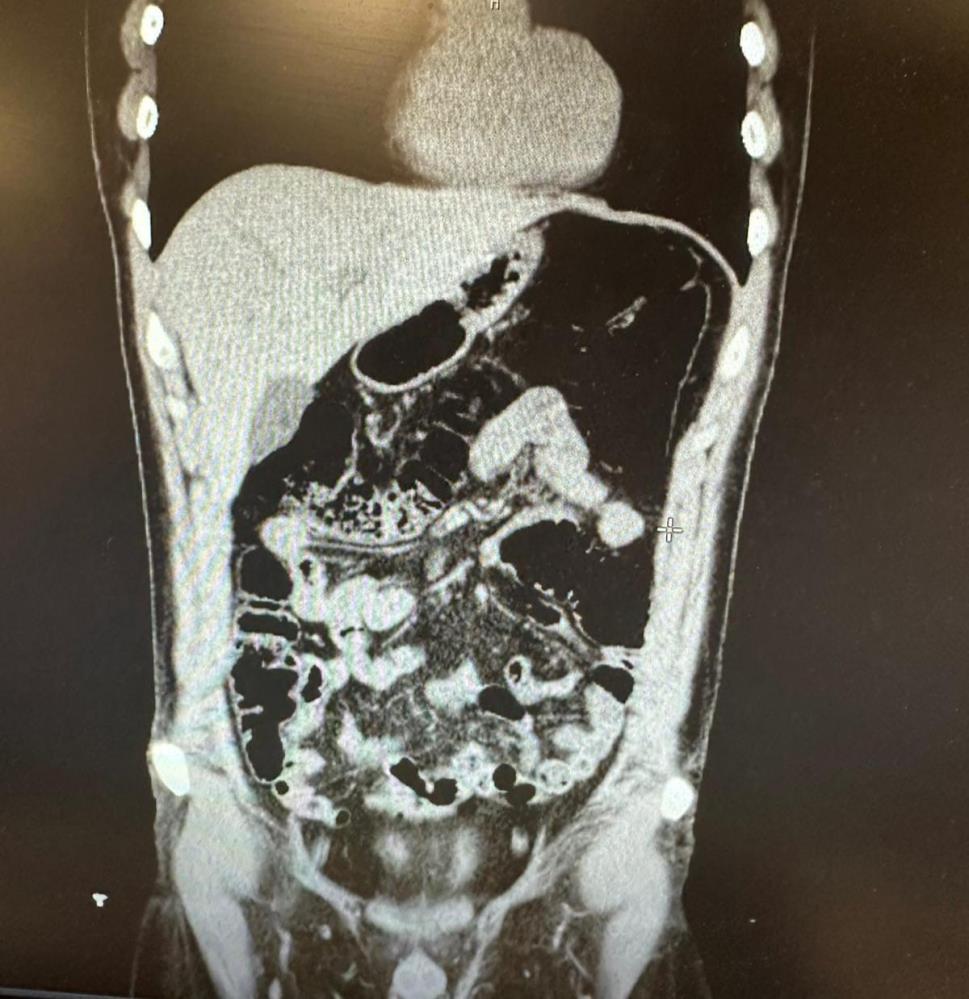

Ekiplerin yürüttüğü saha çalışmalarında uyuşturucu kuryeliği yapan İran uyruklu bir şahıs tespit edildi. Polis, şüphelinin Konya’da gizlendiği adresi tespit ederek operasyon düzenledi. Şüpheli ve beraberindeki 4 kişi gözaltına alındı. Şüpheli, uyuşturucu yuttuğunu ifade etmesi üzerine hastaneye kaldırıldı. Şüpheli, 2 gün boyunca polis nezaretinde hastanede gözlem altında tutularak midesinde kapsüller halinde bulunan eroin maddesi doğal yollarla dışarı çıkarıldı.

Konya’da konakladıkları evin tespit edilmesiyle 1’i İran uyruklu 5 şüpheli yakayı ele verdi. İran uyruklu V.F.G.’nin midesinde 300 gram, gizlendiği adreste Narkotik köpeği Alex ile yapılan aramada ise toplam 6 parça halinde 1 kilogram eroin, bir miktar metamfetamin ve bir miktar uyuşturucu hap ele geçirildi. V.F.G. ile birlikte gözaltına alınan ve uyuşturucu sevkiyatını organize ederek yardım ve yataklık yapan M.P., Ö.T., F.S. ve M.A. uyuşturucu madde ticareti yapmak ve uyuşturucu madde kullanmak suçlarından gözaltına alındı. Daha önce de birçok suç kaydı bulunan şüpheliler sevk edildiği adli makamlarca tutuklanarak cezaevine gönderildi.